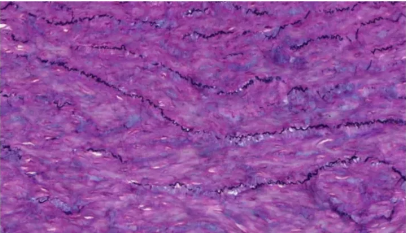

2.Weigert法

用途及原理:适用于所有动物组织石蜡切片,弹力纤维(对较细的弹力纤维尤其适用)。弹力纤维呈紫红色,胶原纤维呈红色,背景其他成分呈黄色。